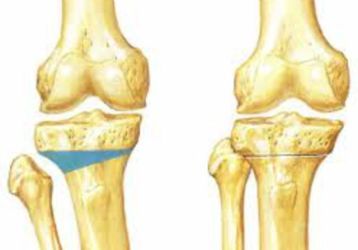

Корригирующая остеотомия: описание, особенности выполнения, возможные осложнения

Показания и противопоказания для выполнения корригирующей остеотомии. Хирургические техники. Осложнения после операции и реабилитация.